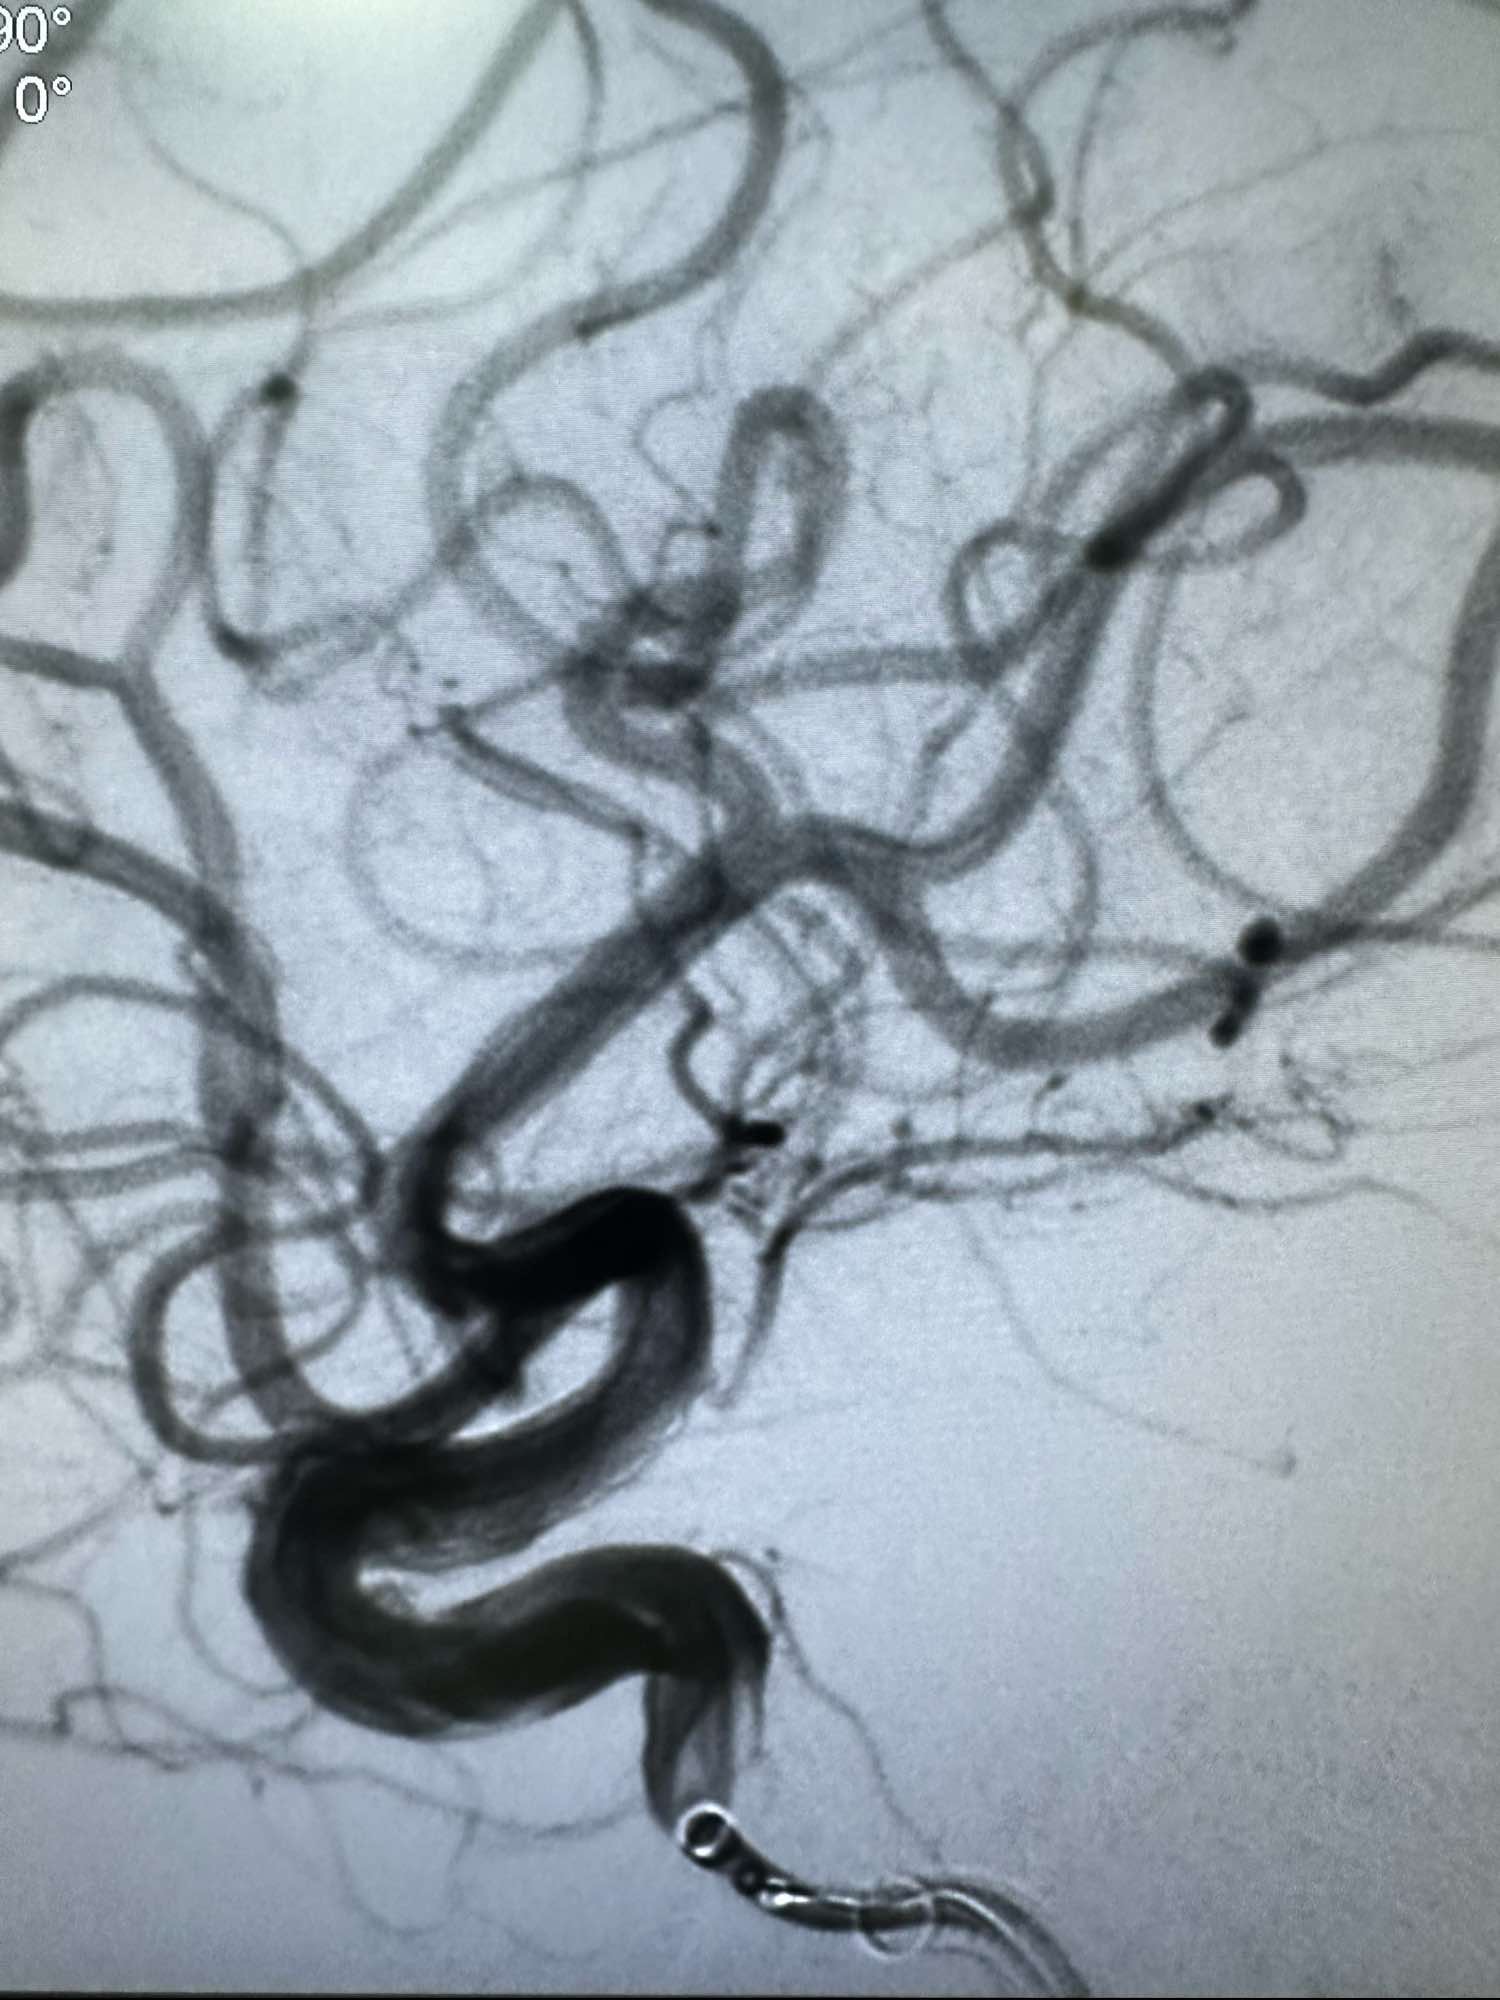

左侧颈内动脉造影正位

侧位